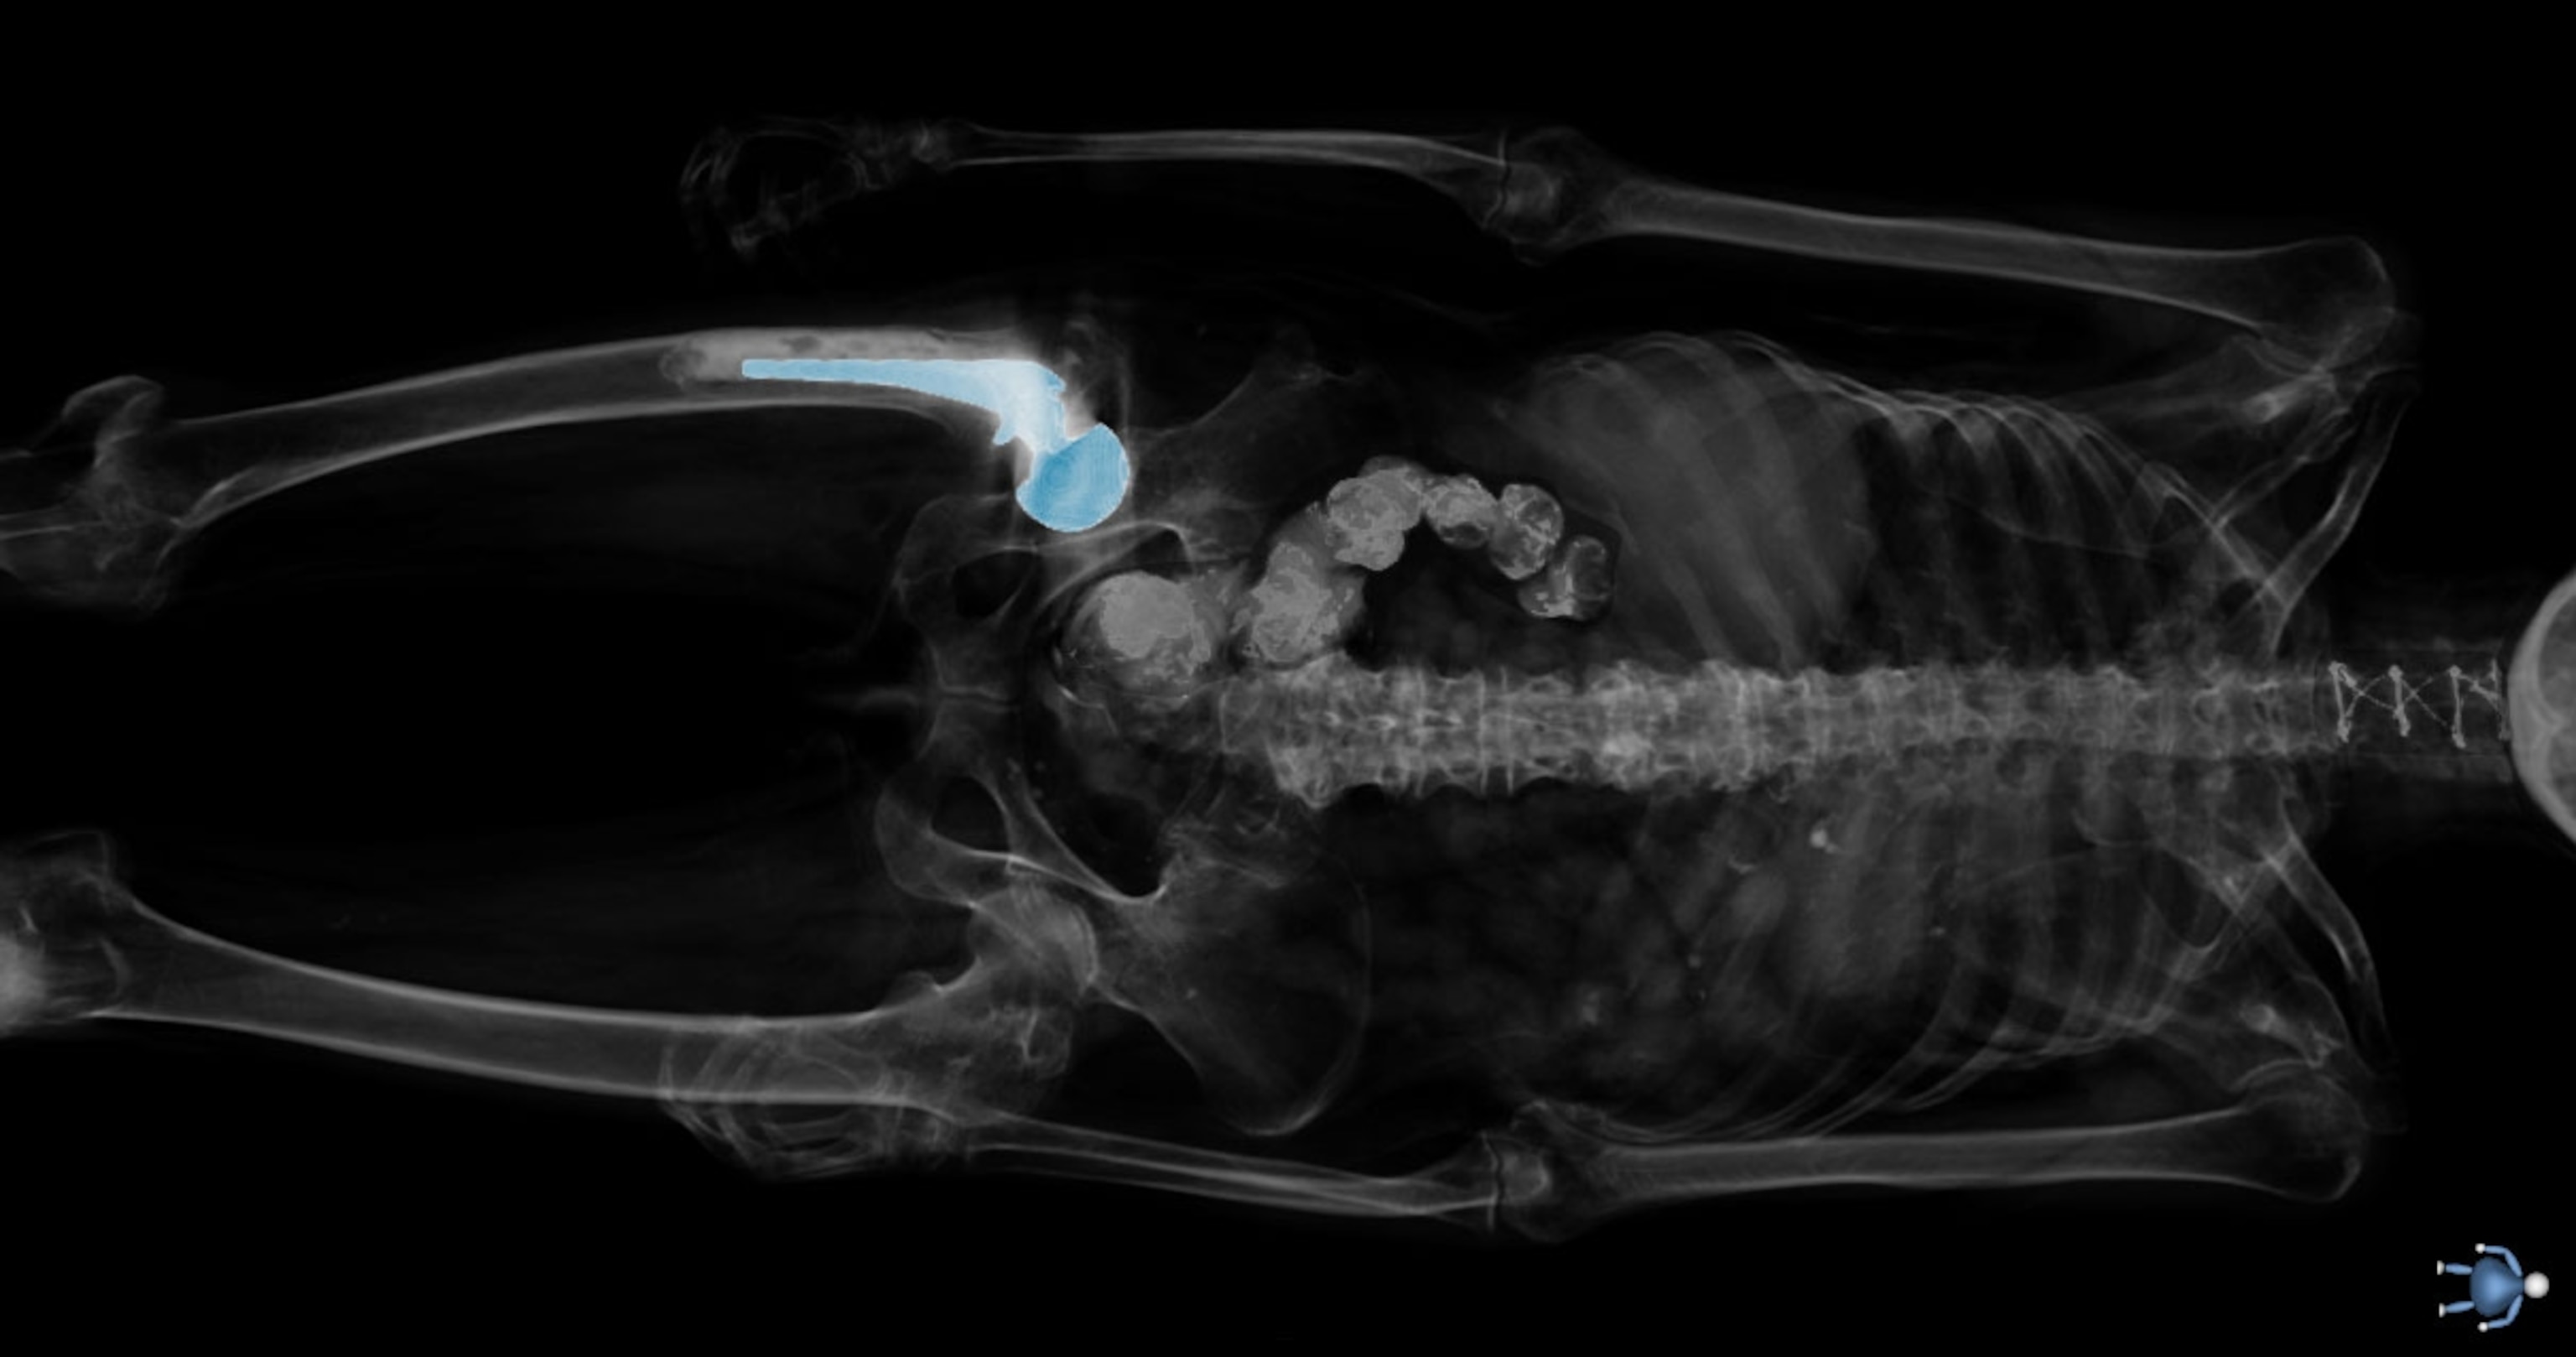

Spitzer placed the torso, encased in a block of blue polyvinyl alcohol, on a stainless steel table in the chilled room. A carbide blade the size of a dinner plate began to grind off tissue in hair-thin, 63-micron increments.

After each pass of the blade, a digital camera photographed each exposed surface of the block. Imagine incrementally sanding a block of wood and photographing the layer of surface grain exposed each cycle. As with a block of wood, what’s left of the corporeal Susan Potter is dust.

At 4:50 p.m., the blade, computerized and capable of running 24 hours a day, began to section her torso, and on a monitor in an adjoining room you could see the brown of liver, the gold of adrenal glands, and the marble of fat and muscle as cross sections of frozen tissue were ground down and photographed. In a bow to another of Potter’s requests, a graduate student streamed classical music into a speaker system.

Cutting the NIH-funded Visible Human Male into roughly 2,000 slices took Spitzer four months in 1993. Twenty-four years later, Susan Potter was cut into 27,000 slices in 60 days. Next comes the painstaking, time-consuming process of outlining the structures—tissue, organs, vessels—on each digital slice to highlight the skeleton, nerves, and vasculature in exquisite detail. That will take two or three years.

Now when Spitzer looks at Potter on the screen in digitized slices, he says, he sees her pain: the tortured, twisted arteries, the steel screws that stabilized her fractured cervical spine, an oddly misshapen kidney, and the arthritic joints that map the relentless decline into old age.